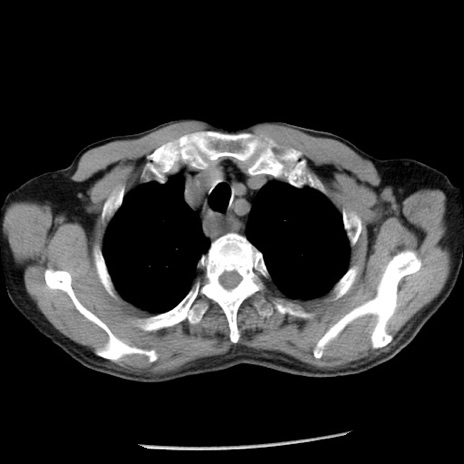

症例26(横断像)

【症例】80歳代男性

【主訴】嘔吐

【現病歴】昨晩2回嘔吐あり、今朝になっても嘔吐あり。来院。

【既往歴】胃潰瘍

【身体所見】意識清明、BT 37.6℃、BP 166/95mmHg、HR 100bpm、SpO2 97%、腹部:平坦・軟、腸蠕動音聴取良好、圧痛なし。

【データ】WBC 21900、CRP 1.46